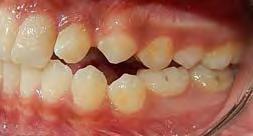

Se presenta una paciente de 13 años 5 meses con el motivo de consulta “es que no me baja el colmillo”. En los estudios extraorales se ve el perfil concavo y labios en contacto durante el reposo (Figura 1). En los estudios intraorales tenemos , clase I esquelética, con crecimiento hipodivergente (Figura 2), clase II molar derecha y clase I molar y canina izquierda, la clase canina derecha no determinada

Figura 1. Perfil, frente en reposo, sonrisa.

(ND), órgano dental (OD) 13 retenido, mordida abierta en sectores laterales, overjet de 3 mm y overbite de 10%, líneas medias dentales desviadas y microdoncia de OD 12 y 22.

Figura 2. Intraorales frente lateral derecha e izquierda. Figura 3. Radiografía panorámica inicial.

Radiografía panorámica final el canino 13 es incorporado al arco (Figura 5) y los terceros molares en etapa de formación.

Estudios intraorales finales en las fotografías oclusales, se ven los laterales 12 y 22, así como la incorporación del canino al arco con torque adecuado (Figura 6). En la lateral derecha e izquierda la restauración estética de los laterales superiores,

Figura 4. Vista oclusal superior e inferior.

sin rotaciones ni discrepancia de Bolton.